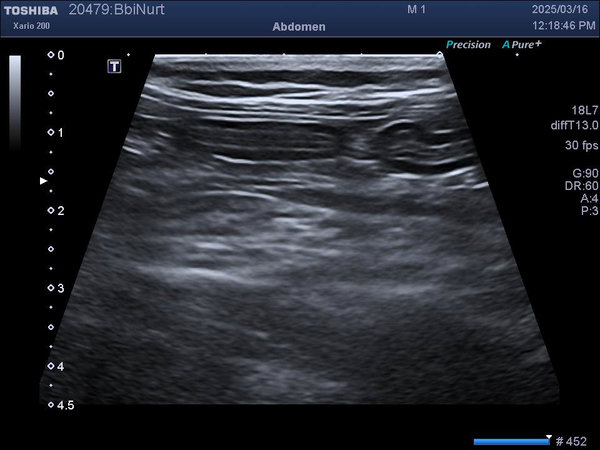

IBD는 증상만으로 확진이 어렵기 때문에, 분변검사, 혈액검사, 복부초음파, 필요시 내시경 조직검사 까지 단계적으로 진행합니다.

폴 동물병원에서는 상태에 따라 단계적으로 검사를 진행하며, 무리한 검사보다 아이의 컨디션에 맞춘 진단을 우선합니다.